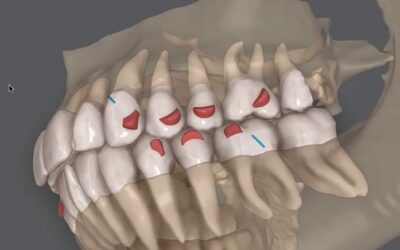

Tomografia integrada ao Clincheck do Invisalign

Recentemente ocorreu uma importante evolução no tratamento Invisalign com a introdução de mais uma avançada ferramenta. Trata-se da integração da tomografia computadorizada cone-beam (CBTC) ao software ClinCheck. Sabemos que qualquer tratamento com os alinhadores...